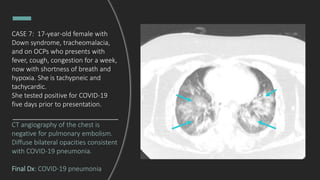

CASE 7: 17-year-old female with

Down syndrome, tracheomalacia,

and on OCPs who presents with

fever, cough, congestion for a week,

now with shortness of breath and

hypoxia. She is tachypneic and

tachycardic.

What do you see?

Multifocal opacities, right worse than

left. Low lung volumes.

DDx: multifocal pneumonia,

pulmonary edema, ARDS.

She tested positive for COVID-19

five days prior to presentation.

CT angiography of the chest is

negative for pulmonary embolism.

Diffuse bilateral opacities consistent

with COVID-19 pneumonia.

Final Dx: COVID-19 pneumonia